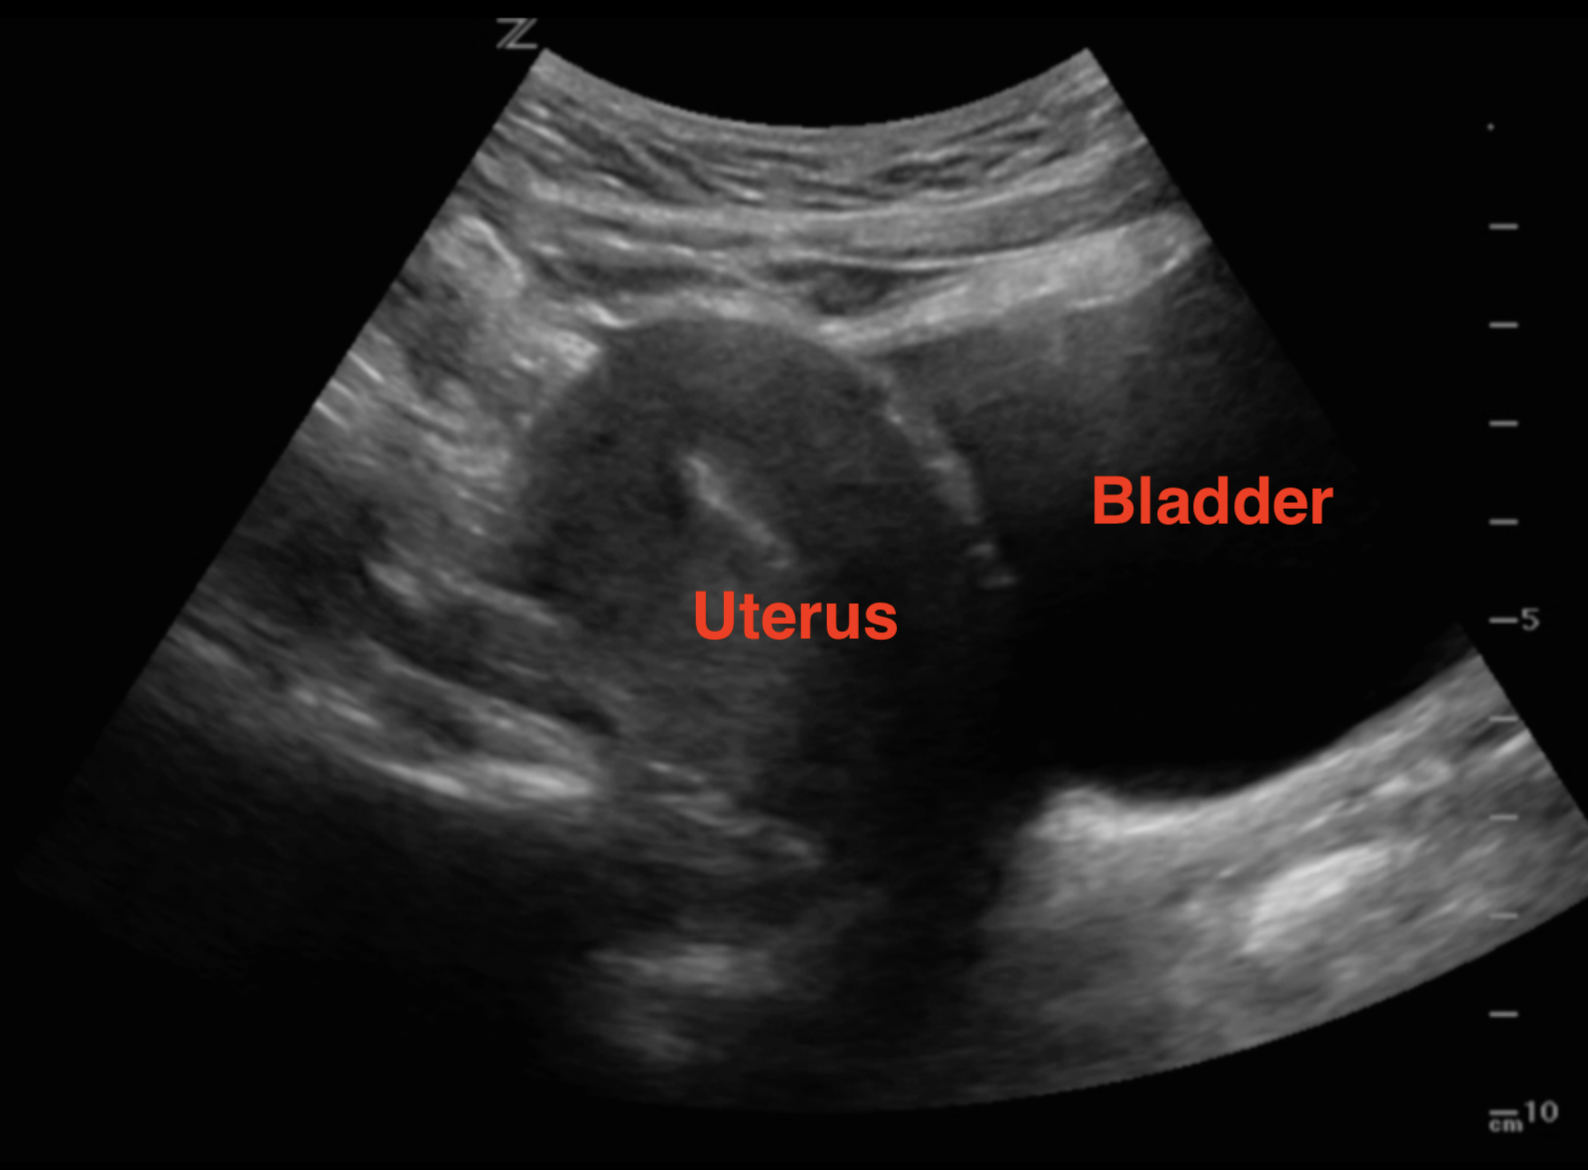

- Rotate the probe towards the patient’s head to and fan left to right in the sagittal plane (Illustrations 5 & 6, Video 2)

- Illustration 6. Pelvis sagittal view with relevant anatomy

- Video 2. Sagittal view with bladder anterior inferior and uterus superior